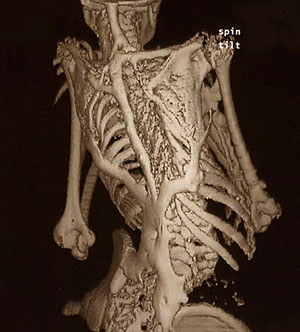

La Fibrodisplasia

Osificante Progresiva (FOP) es una enfermedad genética del tejido conectivo que

se desarrolla en la etapa embrionaria y que se caracteriza por brotes de

osificación heterotópica de ligamentos, tendones o músculos del cuello,

espalda, brazos, pecho y piernas, causando la inmovilidad del enfermo. El hueso

ectópico es química e histológicamente idéntico al hueso normal, sin embargo,

su localización es anómala y provoca gran dolor y una rápida discapacidad.

En la primera o segunda década de

vida el paciente puede presentar brotes de la enfermedad, que se manifiestan

como hinchazones generalmente dolorosos en diversas zonas del cuerpo que duran

varias semanas, los cuales al desinflamarse dejan en su sitio una masa dura de

tejido óseo. Por lo general este problema se presenta primero en cuello y

hombros, y con el tiempo se extiende a tronco, brazos, piernas, cadera,

rodillas y tobillos.

ResponderEliminaruyyyy amigo que feas esas imagenes...terrible ver esa deformidad por la fibrodisplasia